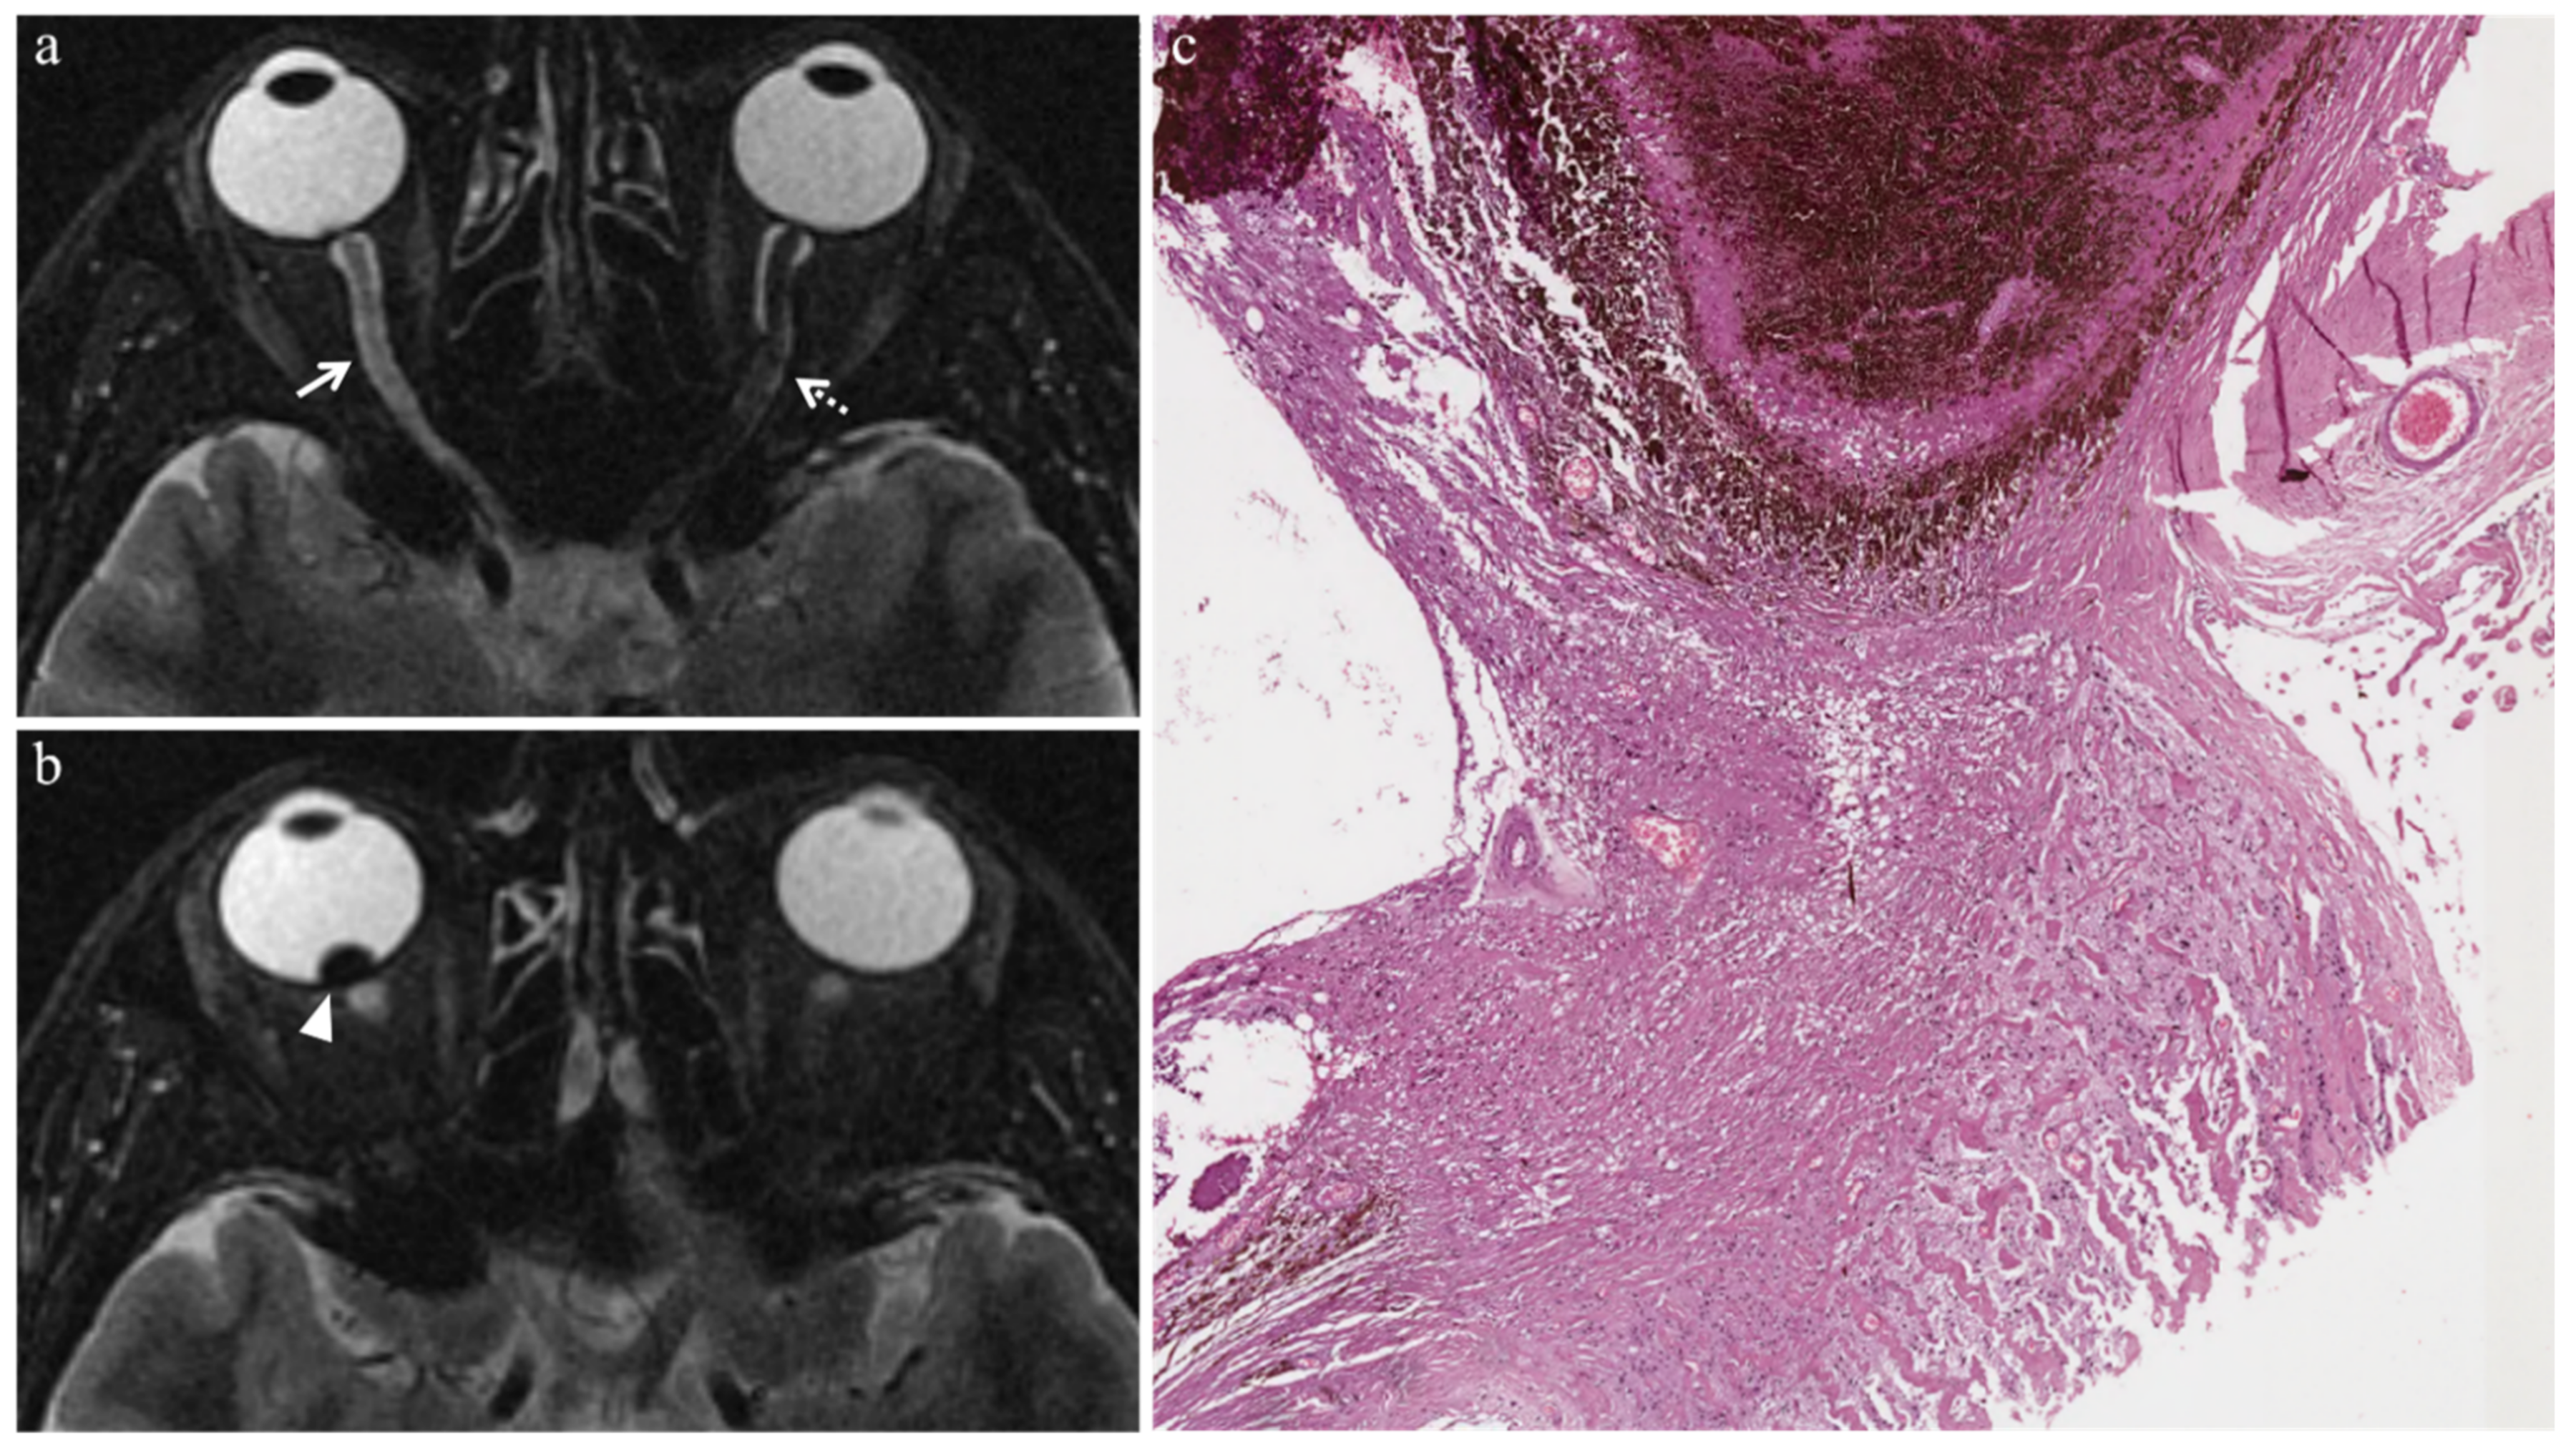

3.2.2. Extratumoral Histopathologic Findings

- Radiation-related intraocular inflammation (uveitis, endophthalmitis, and chronic conjunctivitis) (3/9 patients): presence of a conspicuous inflammatory infiltrate—mainly composed of lymphocytes, plasma cells, and granulocytes—populating the extratumoral ocular tissues.

- Optic nerve degeneration (3/9 patients): gliosis and loss of axonal tissue, which was replaced by fibrosis.

| Patient | Radiation-Related Intraocular Inflammation | Vitreous Hemorrhage | Optic Nerve Degeneration | Iris Neovascularization | Periocular Fibrotic Adhesion |

|---|---|---|---|---|---|

| 1 | - | Yes | - | - | - |

| 2 | Yes | - | - | - | - |

| 3 | - | - | Yes | - | - |

| 4 | - | - | - | - | - |

| 5 | Yes | - | Yes | - | - |

| 6 | Yes | - | - | Yes | - |

| 7 | - | - | Yes | - | Yes |

| 8 | - | Yes | - | - | - |

| 9 | - | - | - | - | - |

enhancement of the viable tissue.| MR Finding | T2 | T1 | Gd-T1 | DWI |

|---|---|---|---|---|

| Uveitis | ![]() High signal | ![]() Low signal | ![]() Enhancement | ![]() High signal |

| Endophthalmitis | ![]() High signal of the anterior chamber and vitreous body on T2-FLAIR | ![]() High signal of the anterior chamber and vitreous body | - | ![]() High signal |

| Chronic conjunctivitis | - | - | ![]() Enhancement | - |

| Vitreous hemorrhage | ![]() Variable signal intensity with possible fluid-fluid level | ![]() High signal of the anterior chamber and vitreous body | ![]() Moderately hyperintense | ![]() High signal |

| Optic nerve degeneration | ![]() Moderately hyperintense | - | - | - |

| Iris neovascularization | ![]() Low signal | ![]() Intermediate signal | ![]() Conspicuous enhancement of the ciliary body | - |

| Radiation-induced cataract | - | ![]() Peripheral high signal | ![]() Peripheral high signal | - |

| Periocular fibrotic adhesion | ![]() Low signal | ![]() Low signal | - | - |

low signal;

intermediate signal;

moderately hyperintense;

high signal;

enhancement;

peripheral high signal;

variable signal intensity with possible fluid-fluid level.Publisher’s Note: MDPI stays neutral with regard to jurisdictional claims in published maps and institutional affiliations. |